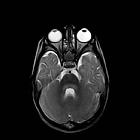

MRI

Brainstem is the most common site of involvement. High signal intensities may be seen on T2-weighted and fluid-attenuated inversion recovery images in the dorsal aspect of the pons, medulla, midbrain, and dentate nuclei . The dorsal aspect of the pons (pontine tegmentum) is the most common site of brainstem involvement . Ventral pontine lesions, substantia nigra and dentate nuclei affection can also be found, but there is usually no supratentorial involvement.